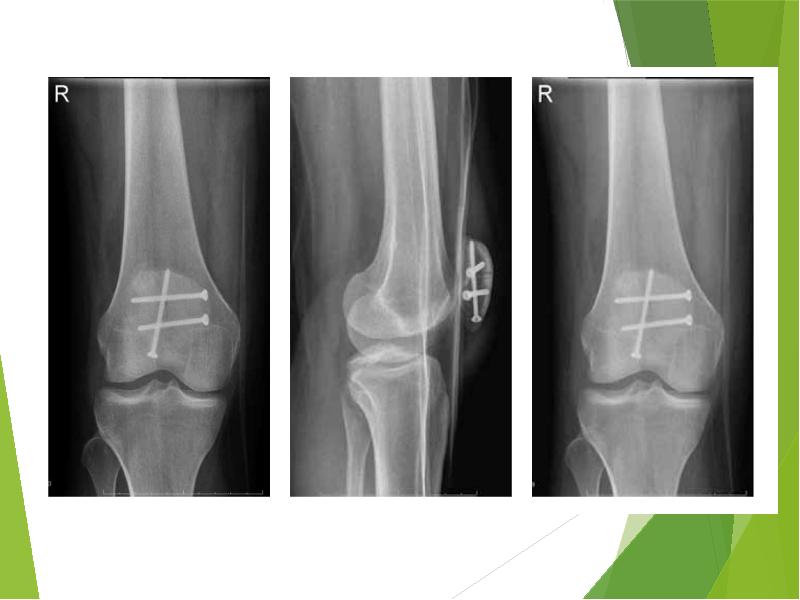

Прямая (слева) и боковая (справа) проекции, на которых виден горизонтальный перелом надколенника со смещением отломков. Осевая проекция. Вертикальный перелом. Обратите внимание на возникшую в результате смещения ступеньку на скользящей поверхности надколенника.

Осевая проекция. Вертикальный перелом. Обратите внимание на возникшую в результате смещения ступеньку на скользящей поверхности надколенника.Иногда для более точного диагноза могут потребоваться компьютерная и/или магнитно-резонансная томография, но, в подавляющем большинстве случаев, достаточно рентгенографии.

Как фиксируют надколенник? Вариант остеосинтеза определяется типом перелома. При поперечном переломе сопоставить и скрепить отломки можно с посощью специальной медицинской проволоки (серкляжа) и спиц. Такую операцию называют именем ее изобретателя – Вебера.

Иногда отломки успешно скрепляются винтами, или винтами и проволокой.

При многооскольчатом переломе также нужно использовать винты и проволоку, которыми скрепляют отломки друг с другом.

Фиксация перелома надколенника винтами.

Наиболее распространённый способ фиксации – это остеосинтез по Веберу, хирургу, который придумал эту операцию. При этой операции для фиксации используются спицы и проволока (продемонстрировано на схеме ниже).

Рентгенограммы после остеосинтеза надколенника по Веберу.